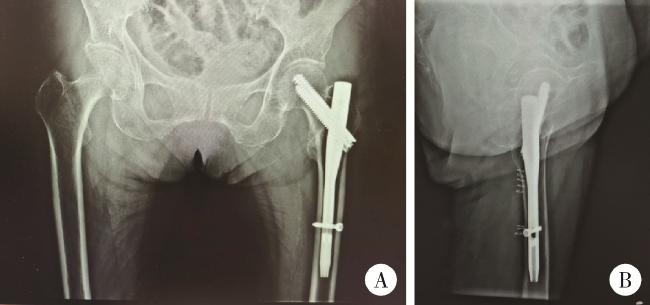

图4 患者术后16个月髋部X线片

Figure 4 Radiographic examination of the hip of patient 16 months postoperatively

A, sixteen months post-operation, X-ray imaging of anteroposterior view of hips; B, lateral view of left hip, revealed a fracture in the left femoral neck and a cut-out screw.